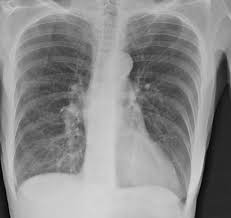

Яки з наведених рентгенограм відповідає спонтанному пневмотораксу.